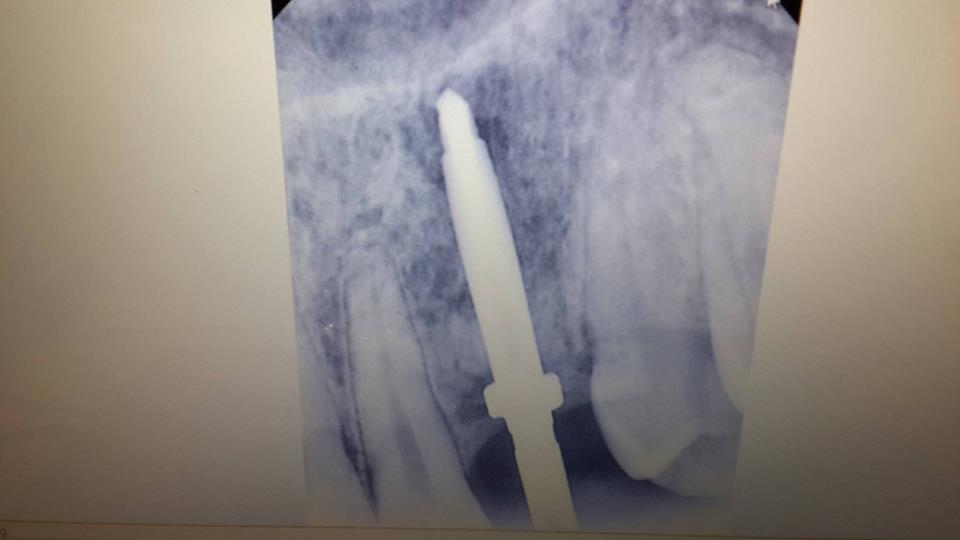

Canine restoration using implantation

To successfully restore the canine, the patient was simultaneously removed a tooth and used bone material.